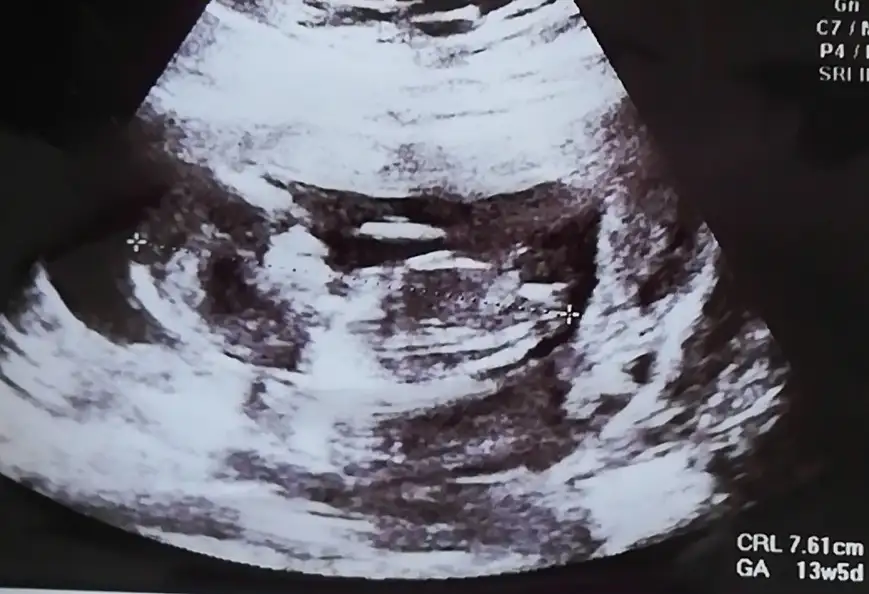

dr soylemeden siz gorun genital nub teorisi ( bebegin cinsiyeti)

Biz bugün gittik ama cinsiyet için erken dedi doktorumz buda yeni fotoğrafımz belki dha nettir

12 haftalık doktor kız gibi dedi ama yanılma çok oluyor dedi 1 ay sonra netleştirirz dedi bazen pipilerini göremiyoruz dedi çok ufak olduğu için yanılabilriz dedi